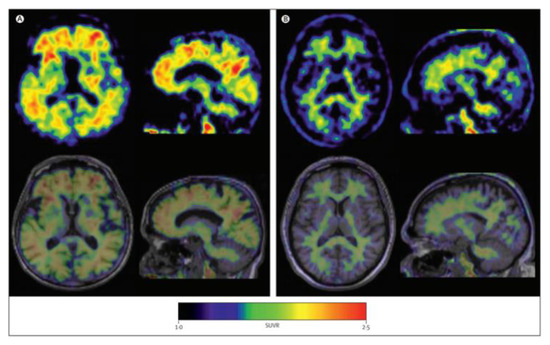

Figure 4.

Axial and sagittal (18F)florbetaben brain PET images of an AD patient (A) and a healthy control (B) for the detection of Aβ [56]. The bottom row illustrates a fused PET/T1-weighted MRI image. Pet images were acquired 90–110 min post-injection. Images are reprinted with permission of the publisher [56].